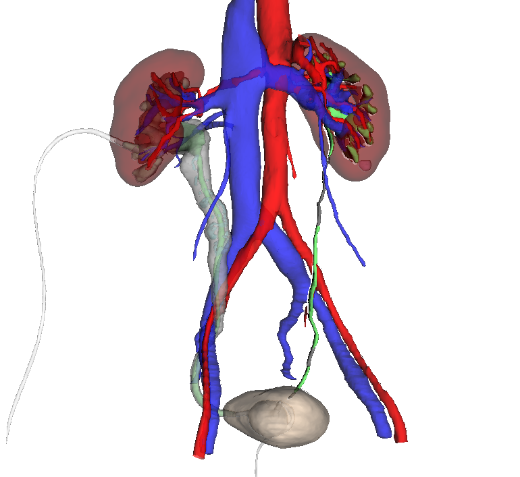

Preoperative Contrast-Enhanced CT with Three-Dimensional Reconstruction

Surgical Plan Simulation Diagram